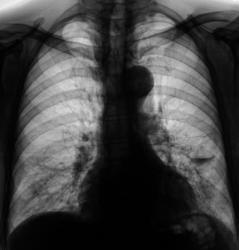

Пациент, при расшифровке флюорограмм, "взят на контроль". Была произведена рентгенография в прямой и боковой проекциях. Пришли к выводу, что имеет место воздушная киста левого лёгкого, содержащая некоторое количество "жидкости".

Согласен с вами. Воздушная киста есть и справа в нижнем поле.

Врожденная патология бронхиального дерева - по типу поликистоза, множественные воздушные кисты и (как говорят студенты) бронхоэкстазы, с признаками активного воспаления...

А может это бронхоэктатическая болезнь?

ИМХО, конечно, но это не похоже на бронхоэктатическую болезнь. Для поликистоза характерно большое колчество кист.